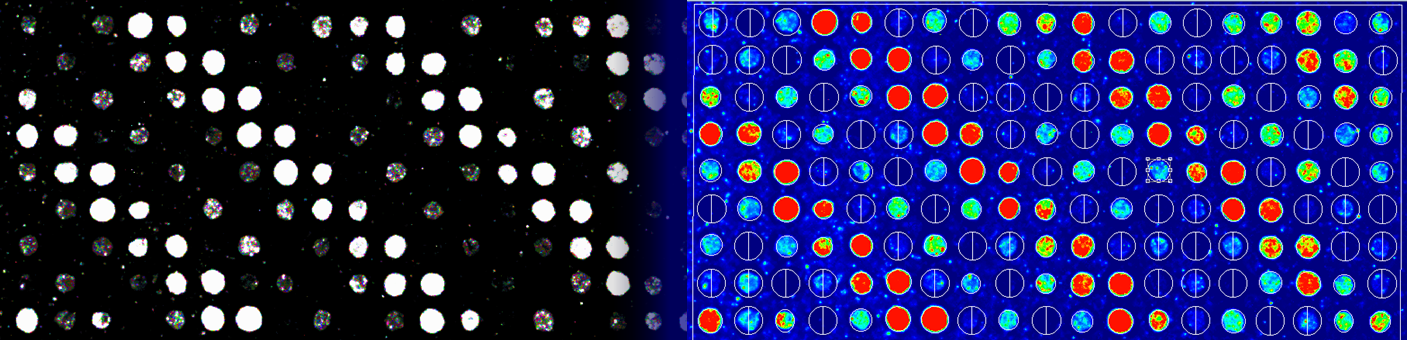

Reverse Phase Protein Array for Mitochondrial Proteins

The RPPA facility hosted in the Department of Biochemistry of the Semmelweis University aims to quantitate the expression of all mitochondrial proteins in healthy and solid tumor samples. We believe that alterations in oncometabolism substantiated by changes in proteins expression 'rewiring' certain metabolic pathways provide an excellent opportunity for cancer-specific therapeutic intervention. Identifying those proteins involved in bioenergetic pathways that are up- or downregulated in order to serve the needs of neoplasia, is crucial for beating cancer.

Our main collaborator is Dr. Leanne De Koning, the Manager of the RPPA platform in Institut Curie in Paris, France, who has been instrumental in setting up our RPPA facility. Furthermore, we plan to collaborate with any group using antibodies directed against mitochondrial proteins in an effort to validate antibodies for RPPA suitability, as well as those groups that can provide large number of samples in lysate format (priority given to human samples).